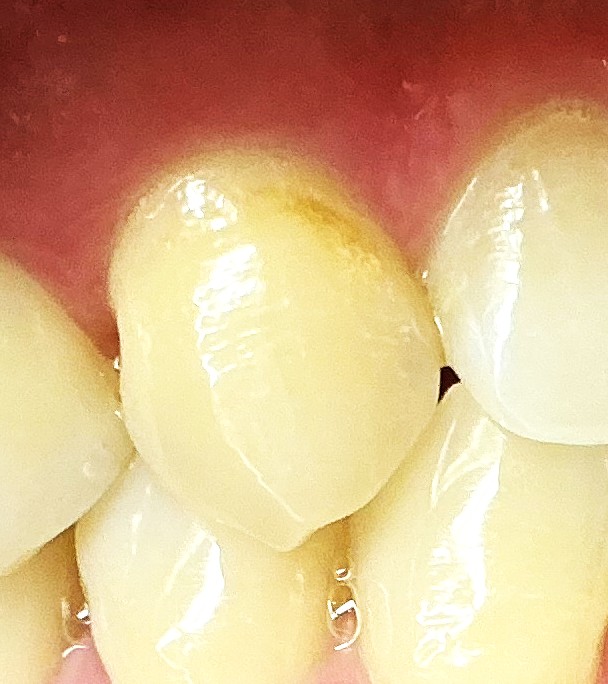

初期虫歯ではシミのようにしか見えないこともあり、主観に頼らざるを得ないため、虫歯かどうかの判断が歯科医師の間でもわかれてしまうことも珍しくありません。

●内部で広がるタイプの虫歯は見つけにくい

虫歯は、広がり方も実にさまざまです。

中には、一見すると小さな穴しかないのだけれども、中で広がっているという虫歯もあります。

このような虫歯が、歯と歯の間の面に生じると、発見することはとても難しいですし、噛み合わせの面に生じた場合であっても気がつかないことも多いです。